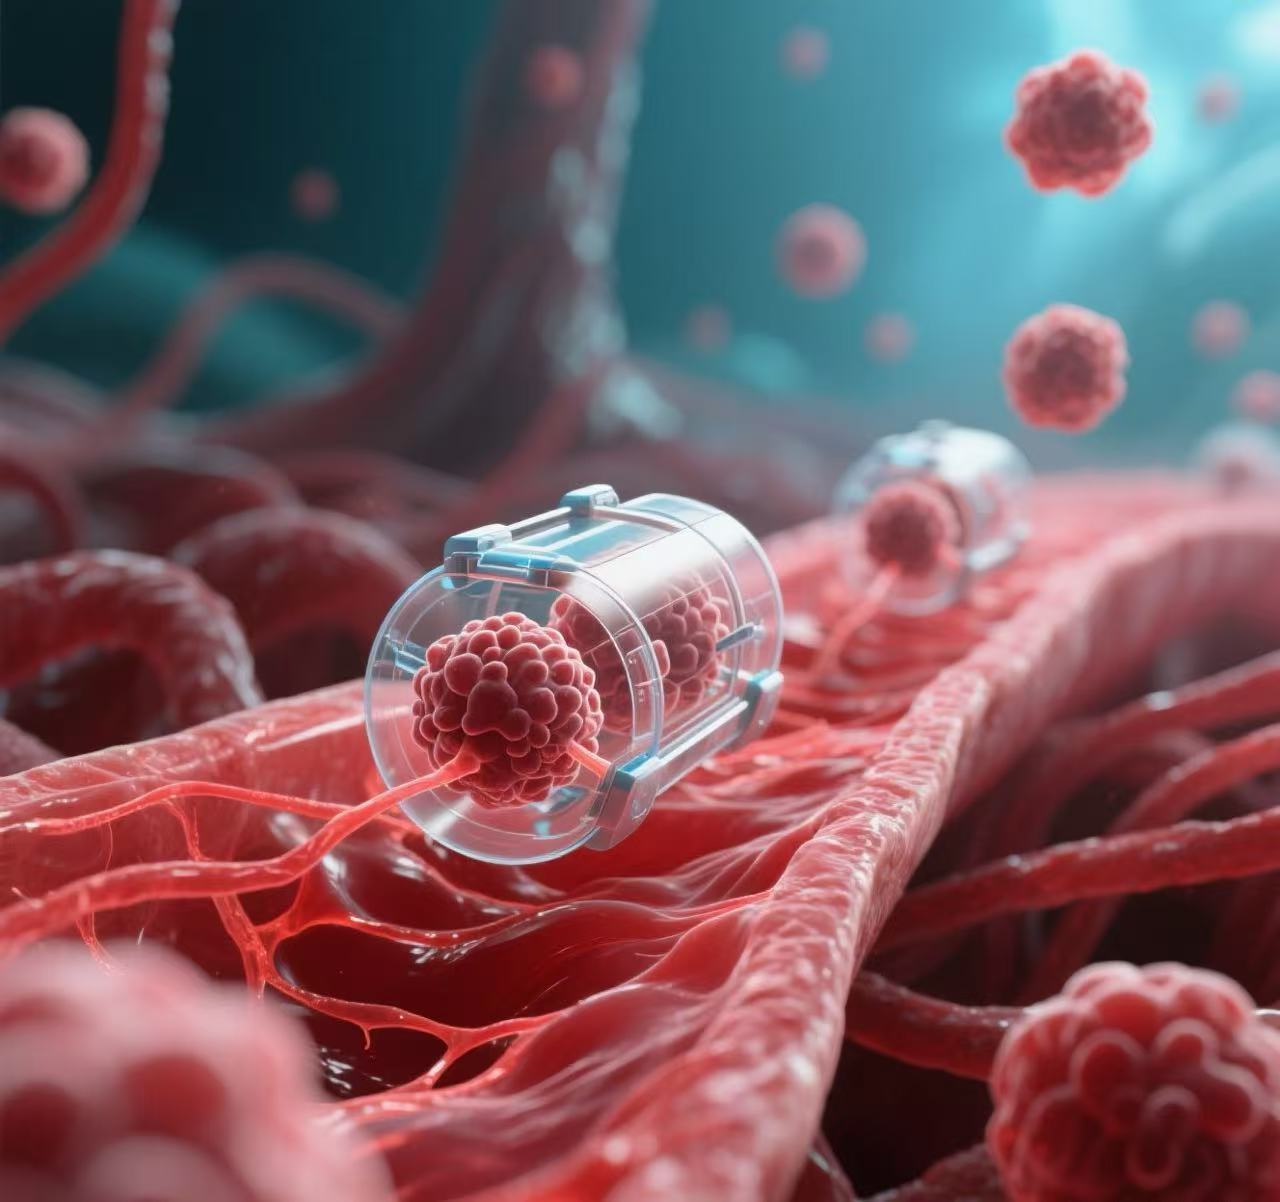

人體內首次持續生成抗癌T細胞